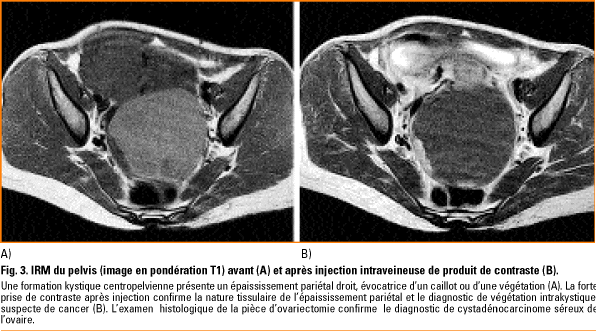

Quelle est la différence entre un scanner et un irm. Radiologie paris ouest rpo groupe de centres de radiologie générale et spécialisée à paris vous propose de vous éclairer sur la différence entre ces deux notions. Lexamen par irm nexpose donc pas le patient aux rayons x. Lexamen se fait dans une machine avec un aimant et peut durer entre 30 minutes et une heure. Très souvent les patients confondent le scanner et lirm alors que ce sont deux techniques très différentes. Lirm utilise en effet un champ magnétique qui crée un signal différent selon les parties du corps observées. Lirm en revanche est un processus plus long du fait de limportance et de la complexité du placement du patient dans le tunnel. Ils ont également des différences fondamentales à lorigine dindications spécifiques selon lâge du patient la région anatomique explorée ou la pathologie recherchée. La plus grande différence réside en ce que lirm fait appel à un gros aimant et à des ondes radio pour générer les images tandis que la tomodensitométrie fait appel aux rayons x. La radiographie est née à la fin du xix e siècle avec lutilisation des rayons x. Scanner et irm ont un certain nombre de points communs importants. Un scanner médical est un appareil dimagerie à rayons x qui permet létude de structures anatomiques en employant la technique par coupes puis par traitement informatique à numériser afin de réaliser des images 2d ou 3d. Aussi certains appareils sont ils dotés dun écran projetant des dessins animés pour les enfants. Différence entre scanner et irm. En effet le scanner utilise les rayons x et se base sur labsorption des rayons par les tissus de lorganisme. Quest ce quun scanner. Même si dans les deux cas le patient est placé dans un tube pour son examen médical la première différence entre le scanner et lirm vient du principe sur lequel la technique repose. Quelle est la différence entre un scanner et une irm. Le scanner utilise les rayons x. Puis de nouvelles techniques dimagerie médicale sont apparues telles que le scanner et lirm imagerie à. Lirm a lavantage de donner des images dans les trois plans de lespace et détudier la colonne vertébrale lombaire dans son ensemble.

Quelle est la différence entre un scanner et un irm. Radiologie paris ouest rpo groupe de centres de radiologie générale et spécialisée à paris vous propose de vous éclairer sur la différence entre ces deux notions. Lexamen par irm nexpose donc pas le patient aux rayons x. Lexamen se fait dans une machine avec un aimant et peut durer entre 30 minutes et une heure. Très souvent les patients confondent le scanner et lirm alors que ce sont deux techniques très différentes. Lirm utilise en effet un champ magnétique qui crée un signal différent selon les parties du corps observées. Lirm en revanche est un processus plus long du fait de limportance et de la complexité du placement du patient dans le tunnel. Ils ont également des différences fondamentales à lorigine dindications spécifiques selon lâge du patient la région anatomique explorée ou la pathologie recherchée. La plus grande différence réside en ce que lirm fait appel à un gros aimant et à des ondes radio pour générer les images tandis que la tomodensitométrie fait appel aux rayons x. La radiographie est née à la fin du xix e siècle avec lutilisation des rayons x. Scanner et irm ont un certain nombre de points communs importants. Un scanner médical est un appareil dimagerie à rayons x qui permet létude de structures anatomiques en employant la technique par coupes puis par traitement informatique à numériser afin de réaliser des images 2d ou 3d. Aussi certains appareils sont ils dotés dun écran projetant des dessins animés pour les enfants. Différence entre scanner et irm. En effet le scanner utilise les rayons x et se base sur labsorption des rayons par les tissus de lorganisme. Quest ce quun scanner. Même si dans les deux cas le patient est placé dans un tube pour son examen médical la première différence entre le scanner et lirm vient du principe sur lequel la technique repose. Quelle est la différence entre un scanner et une irm. Le scanner utilise les rayons x. Puis de nouvelles techniques dimagerie médicale sont apparues telles que le scanner et lirm imagerie à. Lirm a lavantage de donner des images dans les trois plans de lespace et détudier la colonne vertébrale lombaire dans son ensemble. La discussion suivante de la quelle est la différence entre un scanner et un irm que collecter. L'administrateur Diverses Différences 2019 collecte également d'autres images liées quelle est la différence entre un scanner et un irm en dessous de cela. Visitez l'adresse source pour une explication plus complète.